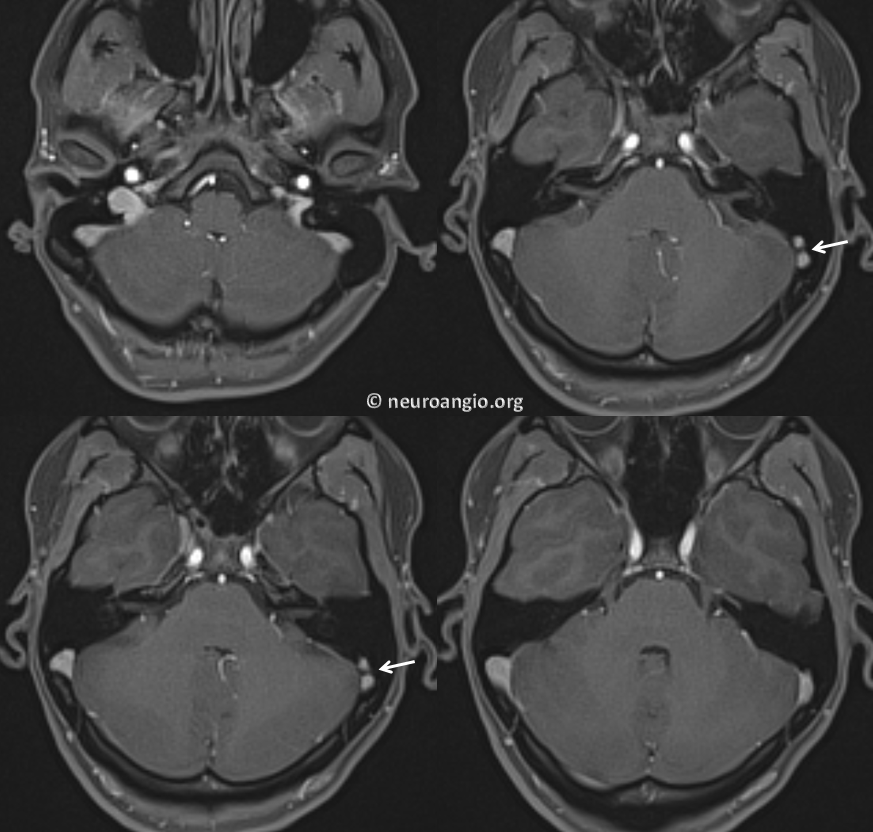

Inferior Petrosal Sinus MRI — some cross-sectional imaging to help identify sinus outflow pathways; inferior petrosal sinus extends along the lateral aspect of the dorsum sella towards the jugular foramen.

Cavernous Sinus=blue; inferior petrosal sinus=light blue; sigmoid sinus=purple